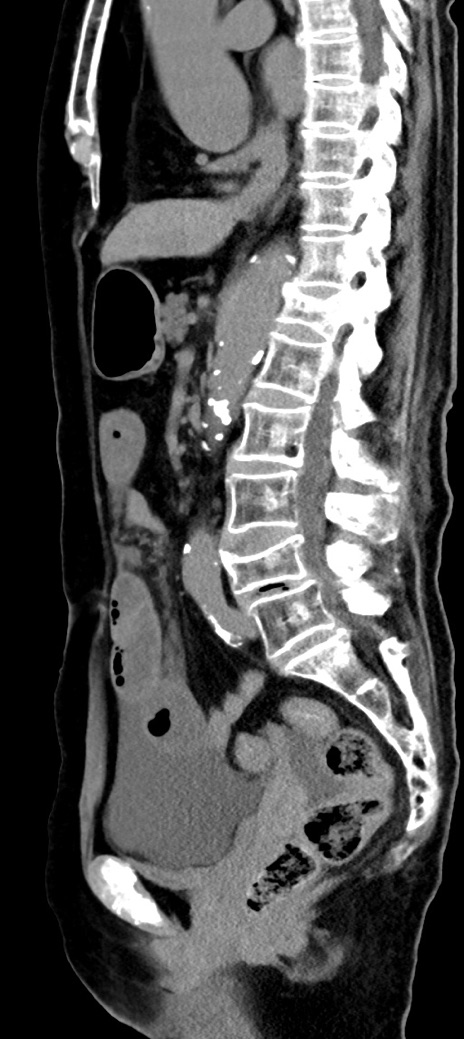

【既往歴】胸椎圧迫骨折、胆石症

横断像

冠状断像